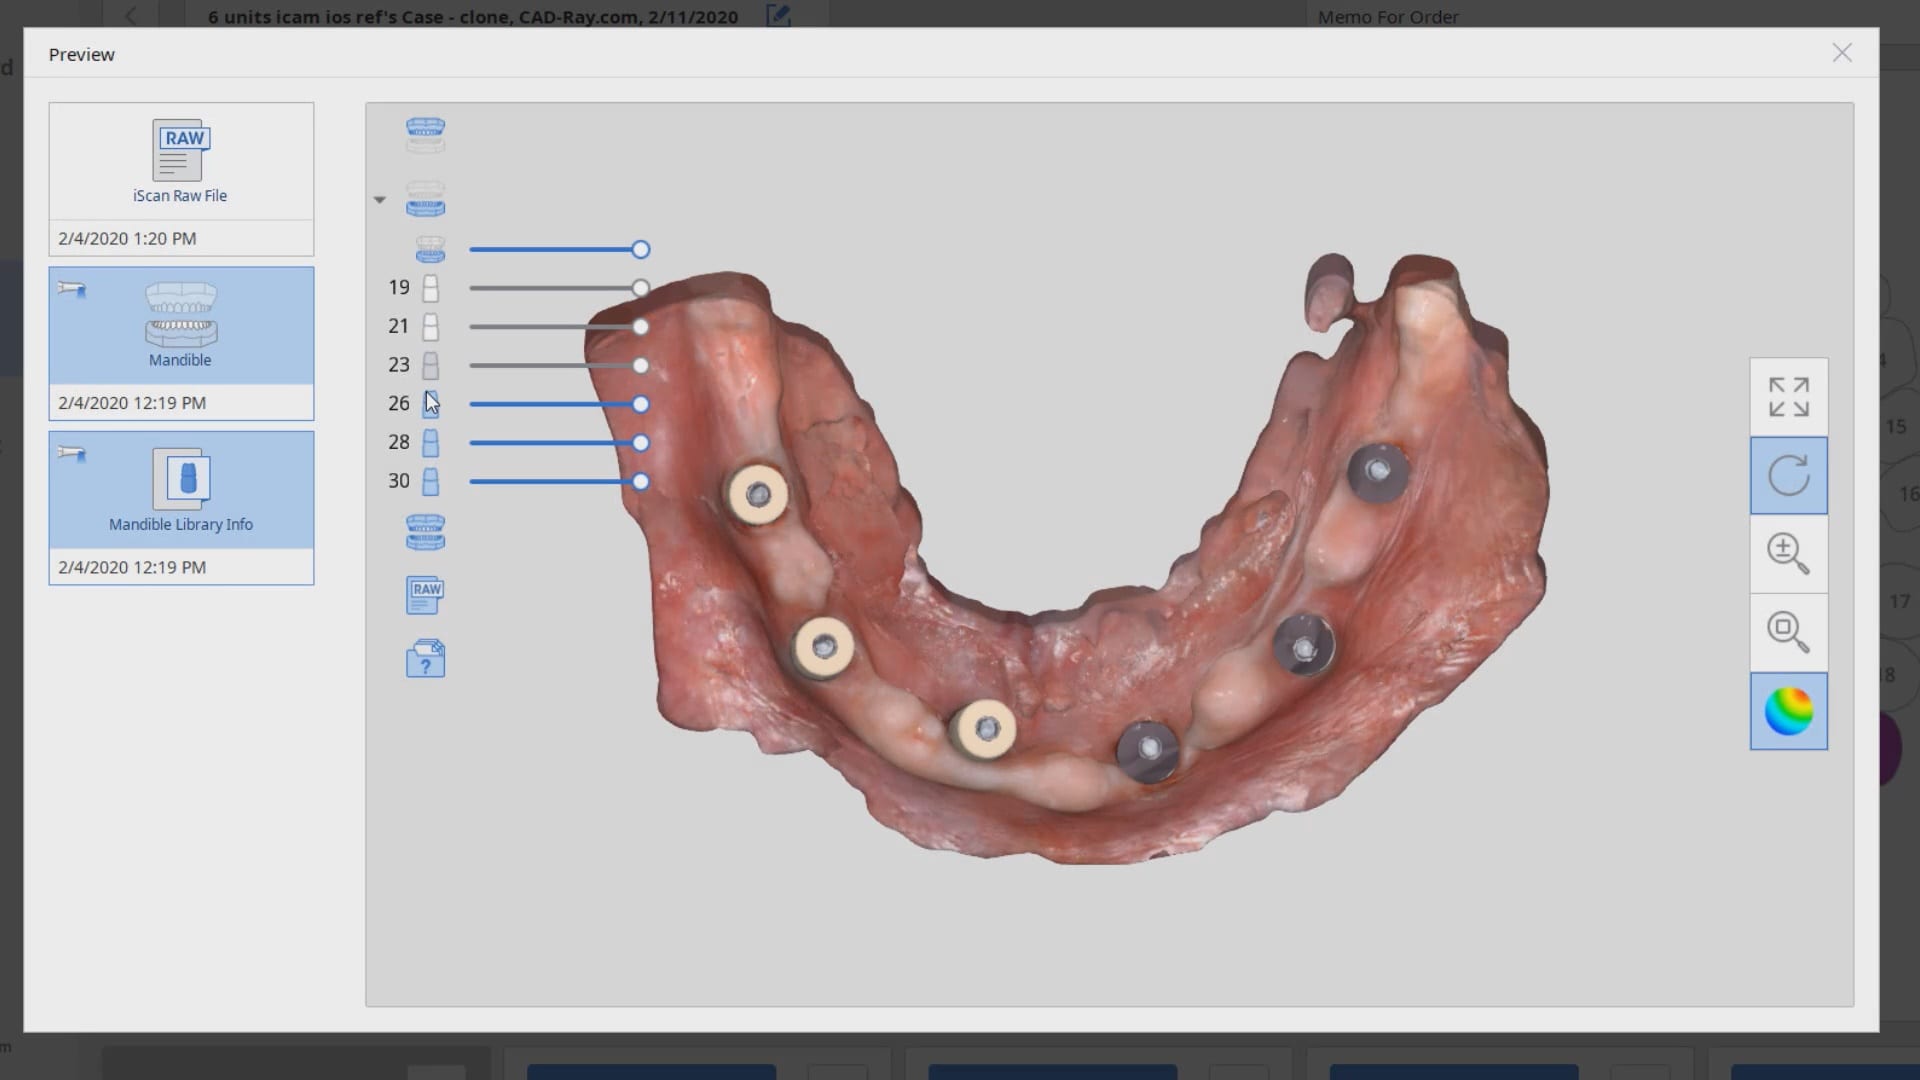

Mixing Photogrammetry and Intra-Orals Scanner by Medit i500

February 4, 2020To date, the literature and research clearly points out that full arch scans with edentulous arches are prone to inaccuracies. That’s because we have never had a way to measure […]